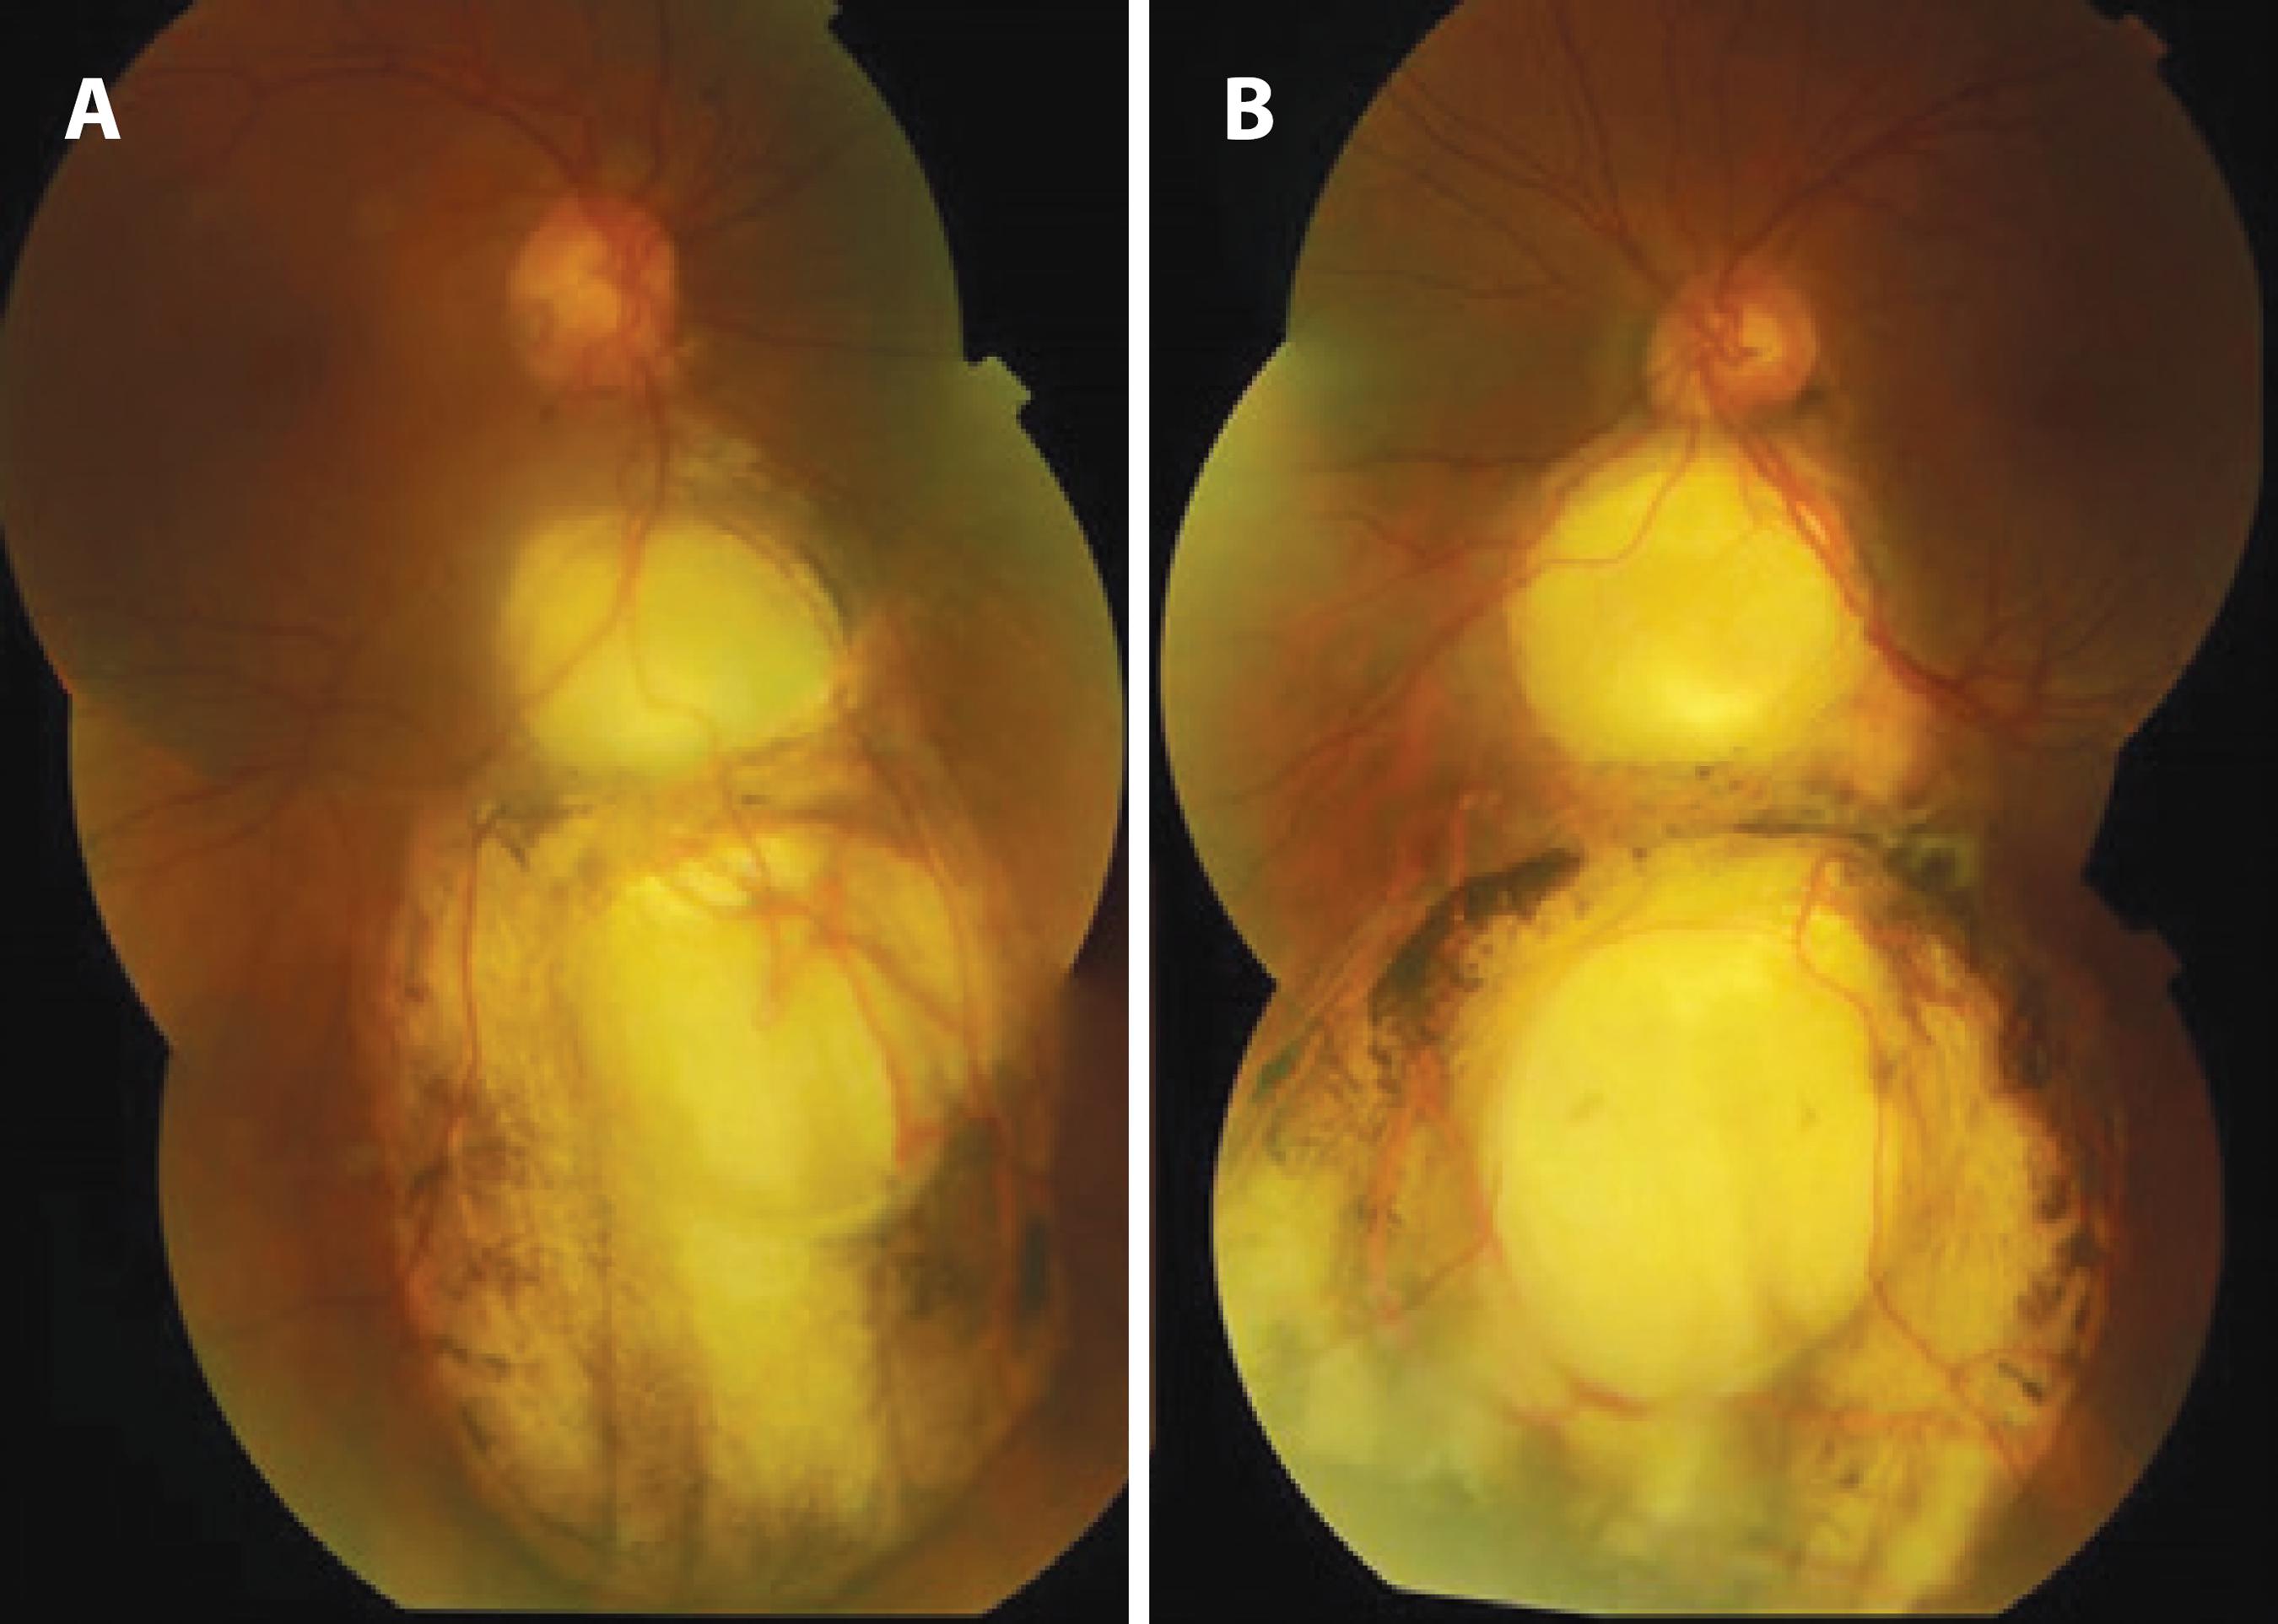

A 42-year-old woman was admitted with a complaint of glare in both the eyes. On ophthalmic examination, her best corrected visual acuity (BCVA) was 20/20 in both the eyes. Biomicroscopic examination of the right eye revealed iris and lens colobomas in the inferior quadrant, pigment precipitates on the lens, and posterior subcapsular cataract (Figure 1 A). In the left eye, there was an iris coloboma in the inferonasal quadrant and iris septa near the limbus that connects the iris tissue, pigment precipitates on the lens, and a lens coloboma in the inferonasal quadrant (Figure 1 B). Bilateral intraocular pressure was 18 mmHg. Fundus examination of the right eye revealed an oval and gray inferotemporal optic pit and two choroid colobomas (one was 2-disc size and an anteriorly located one was 8-disc size, extending to the equator) in the inferior quadrant (Figure 2 A). Under the left optic disc was a 4-disc-sized choroid coloboma that was covered with a membrane with a 1-optic disc-sized hole. A second 7-disc-sized coloboma was detected at the anterior of the coloboma, and pigment alterations were observed around both (Figure 2 B). No retinal detachment was found, and the bilateral maculae were normal. In the right eye, the optic pit revealed hypofluorescence in the early phase and relative hyperfluorescence in the late phase of FFA, as did the bilateral choroid colobomas (Figure 3). Results of optical coherence tomography (OCT) of the optic pit are shown in figures 3 C and 3 D.

Figure 2 A) Optic pit and choroidal colobomas of the right eye, case 1. B) Choroidal colobomas of the left eye inferior to the optic nerve, case 1.